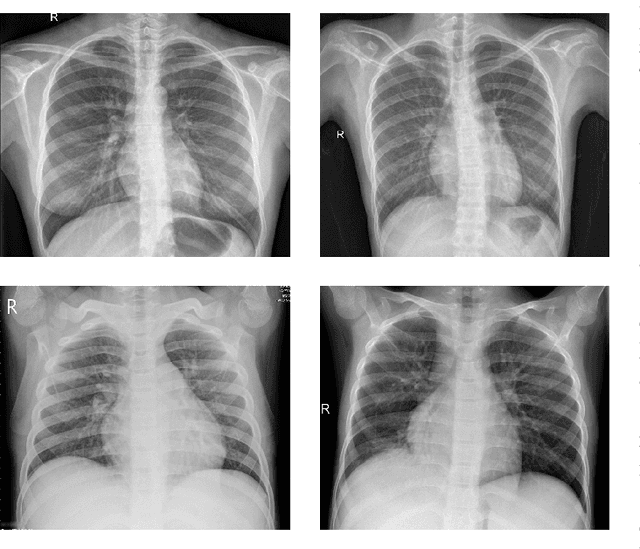

Abstract:Convolutional Neural Networks (CNNs) have proven to be state-of-the-art models for supervised computer vision tasks, such as image classification. However, large labeled data sets are generally needed for the training and validation of such models. In many domains, unlabeled data is available but labeling is expensive, for instance when specific expert knowledge is required. Active Learning (AL) is one approach to mitigate the problem of limited labeled data. Through selecting the most informative and representative data instances for labeling, AL can contribute to more efficient learning of the model. Recent AL methods for CNNs propose different solutions for the selection of instances to be labeled. However, they do not perform consistently well and are often computationally expensive. In this paper, we propose a novel AL algorithm that efficiently learns from unlabeled data by capturing high prediction uncertainty. By replacing the softmax standard output of a CNN with the parameters of a Dirichlet density, the model learns to identify data instances that contribute efficiently to improving model performance during training. We demonstrate in several experiments with publicly available data that our method consistently outperforms other state-of-the-art AL approaches. It can be easily implemented and does not require extensive computational resources for training. Additionally, we are able to show the benefits of the approach on a real-world medical use case in the field of automated detection of visual signals for pneumonia on chest radiographs.